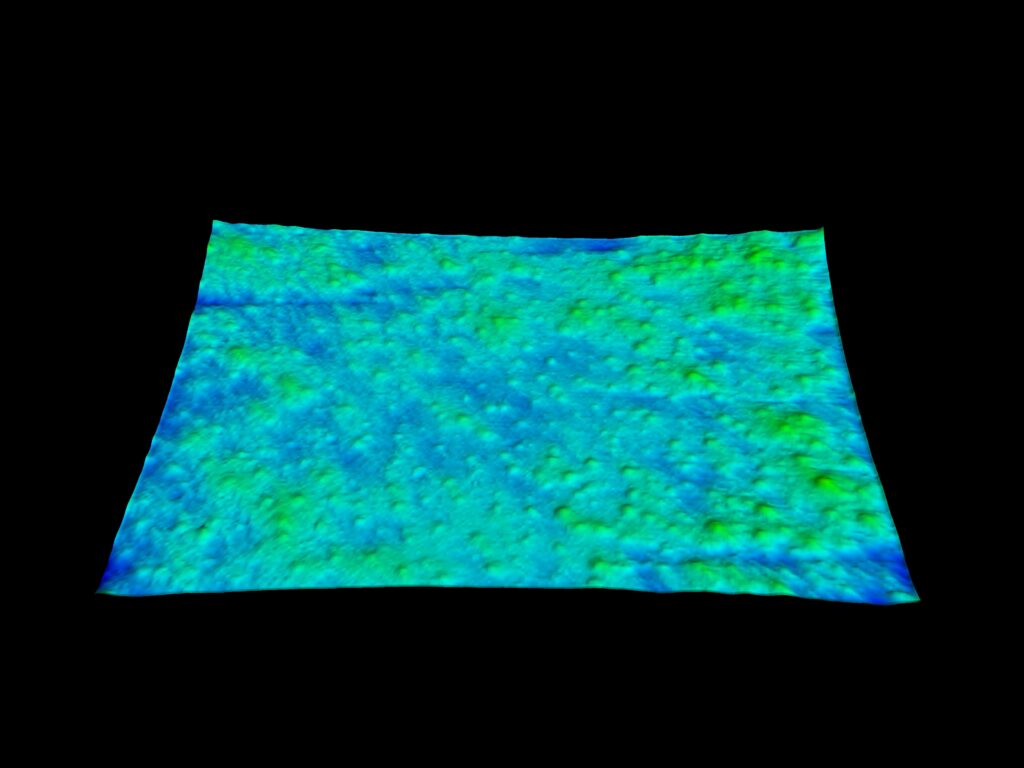

Évaluation de la rugosité

Le C-Cube est indéniablement la meilleure option pour évaluer les changements les plus subtils. Au-delà de la mesure de l’élévation des boutons, il est capable d’observer de très petits signes d’acné avant qu’ils ne s’aggravent avec l’inflammation. Cela revient à mesurer la texture de la peau, invisible à l’œil nu.

Cela peut fournir des informations sur les futurs kystes susceptibles de s’enflammer dans les jours qui suivent.